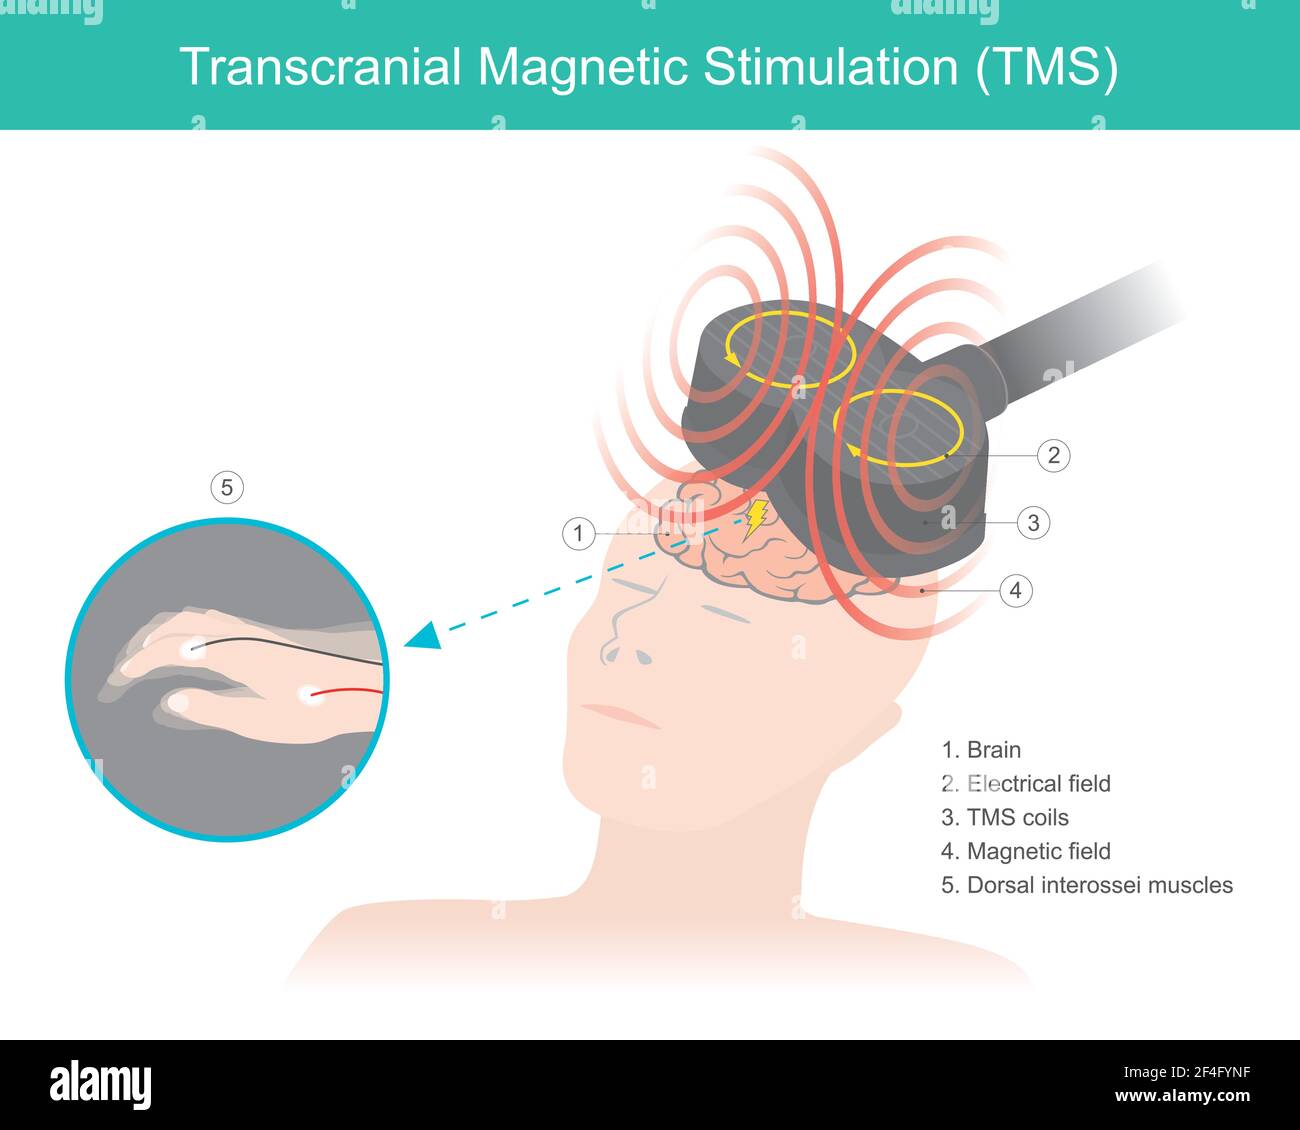

RF2F4FYNF–Stimolazione magnetica transcranica (TMS). La stimolazione cerebrale in cui un campo magnetico variabile viene utilizzato per causare corrente elettrica. Assistenza sanitaria e io